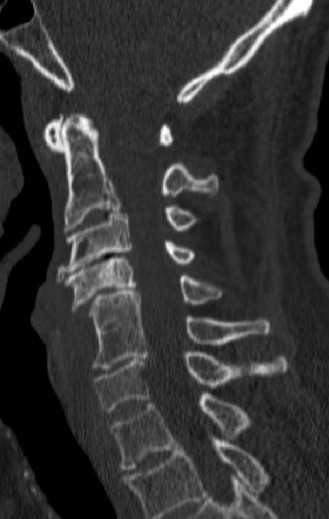

- CT Scan: Provides detailed bony anatomy, identifies fractures, osteophytes, and can assess spinal canal dimensions. CT angiogram may be considered if vertebral artery injury is suspected, particularly in fracture-dislocations.

The classic mechanism for CCS is a hyperextension injury in a patient with pre-existing cervical spondylosis and spinal stenosis.

Spondylosis:

Degenerative changes (osteophytes, disc bulging, ligamentum flavum hypertrophy) narrow the spinal canal.